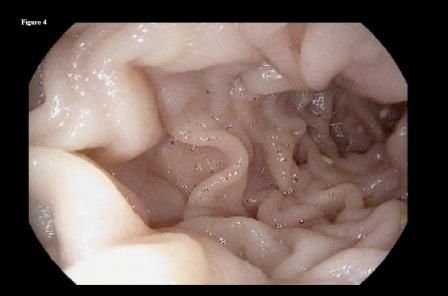

Figure 4.

She followed this regimen for the following 3 months with significant improvement in her symptoms. A repeated upper endoscopy performed at 3 months after presentation showed complete dissolution of the phytobezoar, with a clear view of the distal end of the gastric remnant (Figure 3) and the jejunal side of the anastomosis (Figure 4).